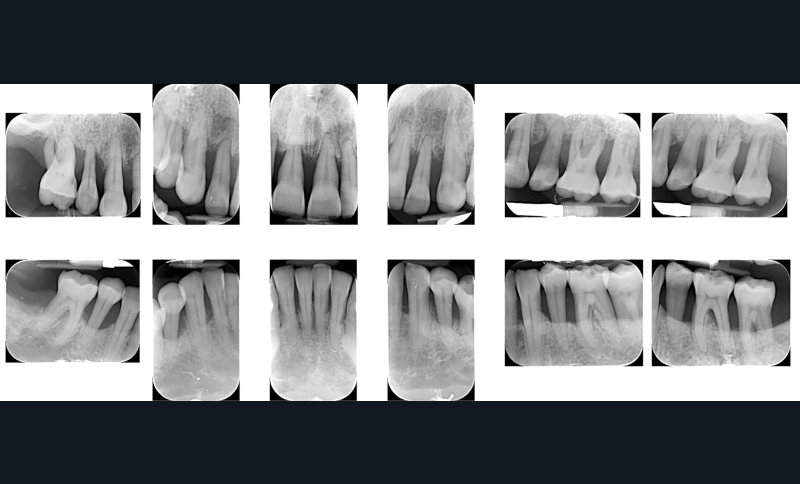

Avant toute intervention chirurgicale, un assainissement parodontal a été effectué. Les deux arcades ont été traitées afin de stabiliser l’environnement biologique (fig. 1). L’analyse complète du volume osseux et gingival a donc été réalisée à partir d’une situation clinique compatible avec une prise en charge implantaire ; un parodonte sain réduit (fig. 2).